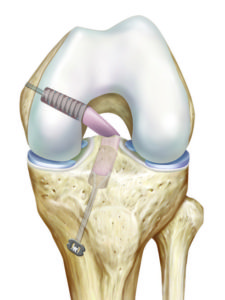

Die Befestigung des in den meisten Fällen abgerissenen Hinterhornes des Meniskus führen wir minimalinvasiv mittels Gelenkspiegelung durch. Hierbei wird die abgerissene Wurzel mit einer speziellen Nahttechnik und einem sehr stabilen Fadenmaterial armiert. Anschliessend wird der Bereich, in dem der Meniskus ausgerissen ist, angefrischt. Mit einem kleinen Bohrer wird nun durch den Unterschenkel ein Kanal gebohrt, durch welchen dann die an der Wurzel befestigten Fäden nach vorne ausgeleitet werden. Hier erfolgt dann unter Zug die Befestigung des Meniskus, exakt an der Stelle des Ausrisses, indem die Fäden vorne am Knochen befestigt werden. Dies kann mit einem kleinen Metallplättchen zusätzlich verstärkt werden.